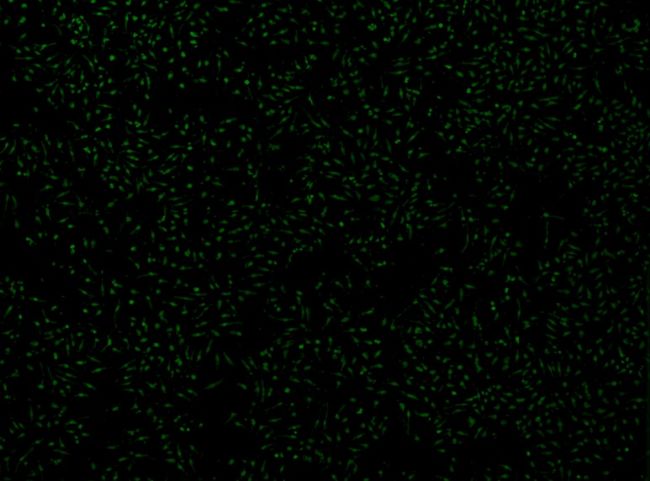

活細胞成像通過實時監測細胞在轉染過程中的動態變化,幫助評估轉染效率、基因表達和細胞健康狀態。在細胞轉染實驗中,利用熒光標記的轉染分子和報告基因(如GFP),可以觀察轉染分子進入細胞、分布及其對細胞功能的影響。此外,活細胞成像還能夠跟蹤細胞存活、增殖、遷移等行為,評估轉染對細胞的生理影響,從而為轉染技術的優化和基因功能研究提供關鍵數據。

| 總細胞覆蓋率(14.1%) |

轉染細胞覆蓋面(6.1%) |

Celloger 活細胞成像監測CHO細胞生長過程